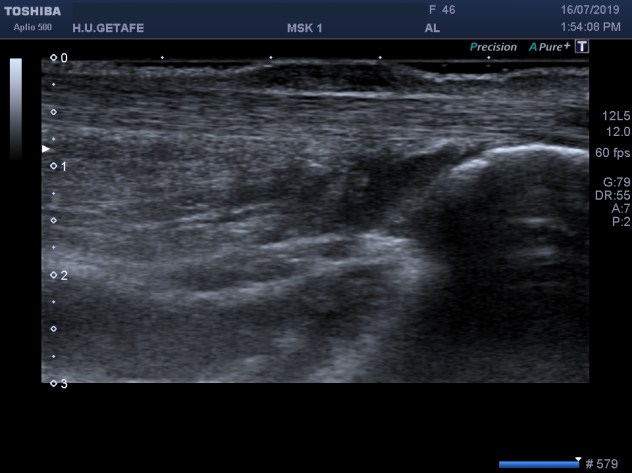

La exploración del Aquiles estándar en este caso revela un aquiles perfectamente normal, hiperecogénico, sin aumento de calibre. Existe a cinco centímetros de la inserción una lesión ovoidea, superficial, heterogénea, extramuros del Aquiles, justo debajo de la piel, dolorosa, no capta señal doppler. Grasa de Kager conservada.

La lesión no comprime al tendón y es compresible. Imagen 8.

En la imagen 2 puedes ver como la lesión no corresponde ni está en contacto con el aquiles, pertenece claramente al tejido celular subcutáneo.